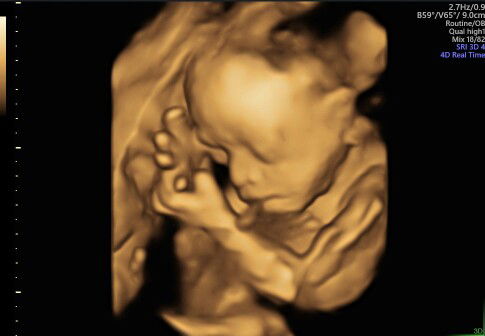

Bingung...perkiraan lahir menurut http 8desrmber,tpi liat hasil usg,,hpl nya 22agustus

Saya hpht 15 November HPL usg 14 agustus, hpl bidan 24 agustus, hpl aplikasi 22 agustus

mungkin maksud mak ts nya hpht nya 8 desember 2020 tapi hpl nya 22 agustus 2021.